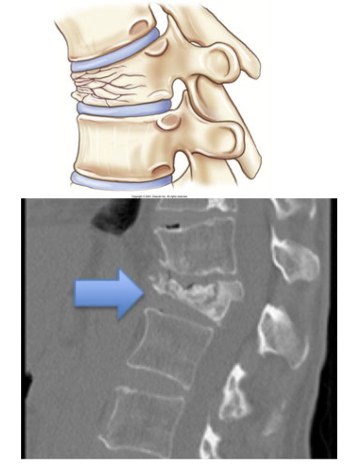

What type of fracture is this?

Compression

What is a compression fracture?

Vertebral fracture displays as decreased vertical dimension of anterior vertebral body

Lower t-spine usually